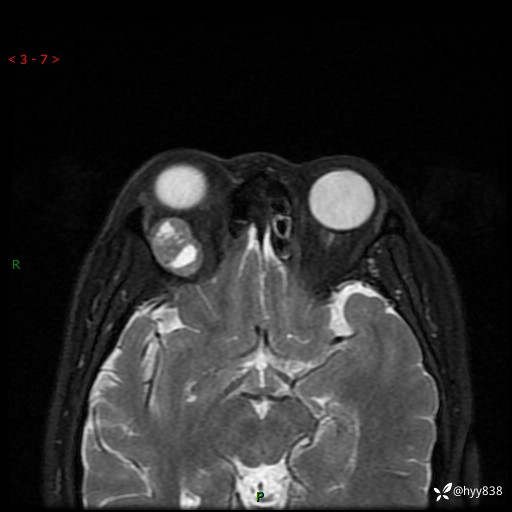

老年女性,右眼球突出1月。说说鉴别诊断,看谁第一个秒---(有结果)

主诉:发现右眼球突出1月余

简要病史:患者于1月前无明显诱因发现右眼球突出,偶感磨痛、眼胀,无视力下降,无头痛,恶心呕吐等不适。10天前就诊于当地县人民医院就诊,完善头颅ct检查,诊断为右侧眼眶肿物,建议患者上级医院进一步治疗,患者因个人原因拒绝。拟行手术,来我院就诊,门诊行相关检查后以“右眼眼眶肿物”收入院。 患病以来,患者精神饮食睡眠尚可,大小便如常、体重无明显改变。

辅助检查:MRI

临床诊断:眼眶肿物

眼眶MRI平扫+增强